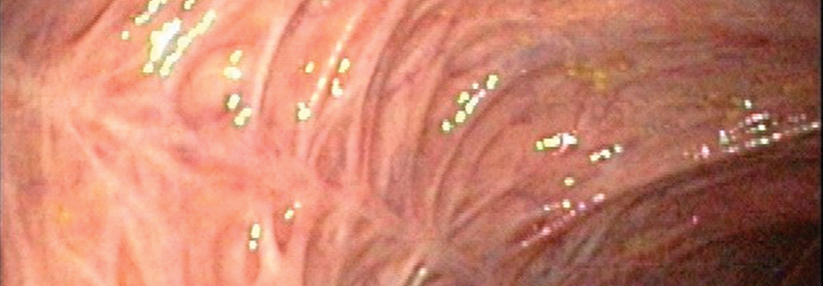

Mit Atemtest oder Endoskopie die Dünndarmfehlbesiedlung erkennen und behandeln

Wenn sich im Dünndarm zu viele Bakterien tummeln, bleiben Blähungen, Obstipation und Krämpfe meist nicht aus. Die SIBO ist ebenso komplex wie…